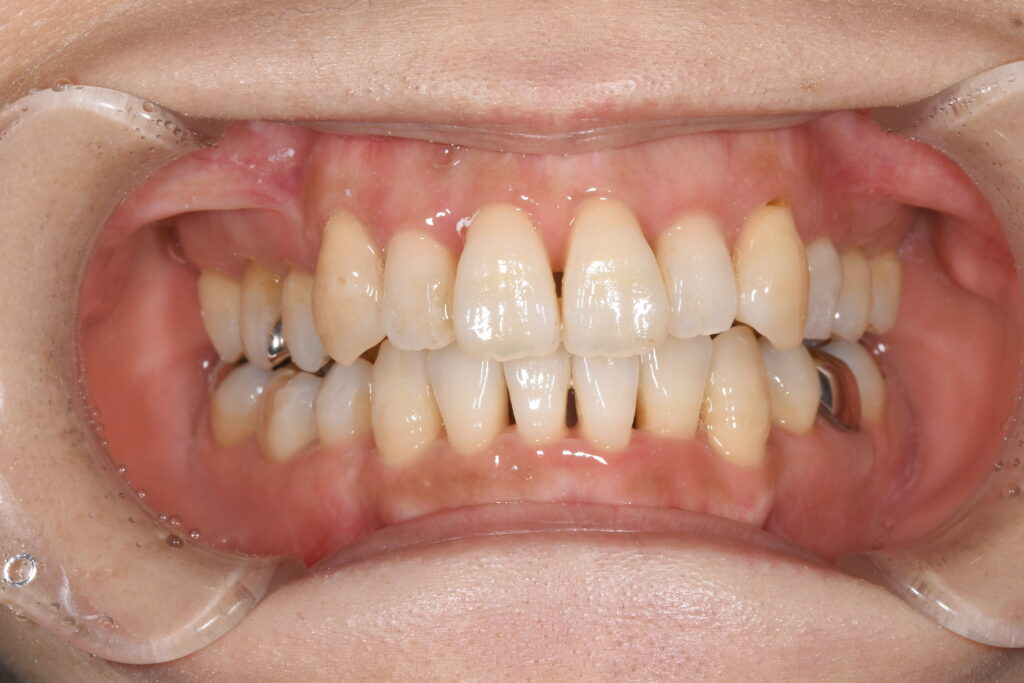

以下に術後8カ月の状態です。(まだ、微調整が必要なため終了ではありません)

【矯正開始8カ月後】

いかがでしょうか。

マウスピースを適切に使用して頂けたおかげで、ここまで改善することができました(^^♪

患者様にも大変喜んで頂き、うれしい次第です(^^)/

この患者様は合計4本の抜歯を行いこの状態になりました。

インビザラインでの治療を行う際は、歯型を取り、コンピューターでどのように歯を動かすかシュミレーションを行います。その際、歯を抜歯しなくても済む計画を立案できることもありますが、今回は抜歯を避けることができませんでした。

ただ、抜歯をしても、針金を使用せずここまでの状態に歯並びを改善することができるのです!

インビザラインでは、このコンピューターシュミレーションがかなり重要となります。どのように歯を動かすのかを決定するのは歯科医師です。ですので、他院で同じようにインビザラインで治療を行っても、終了時の状態には差が出ますし、抜歯を行った場合は、インビザラインではできないとお話されるのは、その先生のお考えによるところが大きいのです。

しかしながら、確かに全ての歯並びをインビザラインだけで改善できるとは私は思っていません。実際に、お断りした患者様のいらっしゃるのは事実です。ですが、現在ではほとんどの歯並びに対応できるようになっております!